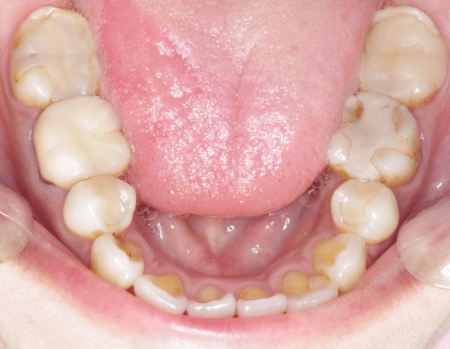

小臼歯を抜歯して矯正したことで残存した小臼歯と大臼歯のかかる負担が大きく破折・虫歯のトラブルを引き起こします。写真では歯列弓が狭くなり舌の置き場所がなく、舌の後退や沈下を引き起こしやすく、息苦しく見えます。

小臼歯抜歯した患者様の口腔内

舌が窮屈そう。奥歯は再治療が続いている。